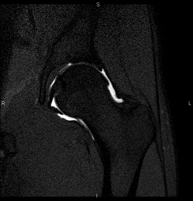

Exploració per estudiar les lesions en petites estructures anatòmiques de l'articulació que solen produir-se en pacients que pateixen luxació o pinçament (disminució de l'espai). L'estudi ve precedit per una injecció de contrast a l'interior de l'articulació, realitzada sota control de raigs X. La durada total dels dos procediments és de 50 minuts. - Artro-RM de Genoll

Exploració per a l'estudi de les lesions en petites estructures anatòmiques de l'articulació, com ara el cartílag i els meniscs, principalment els ja operats. L'estudi ve precedit per una injecció de contrast a l'interior de l'articulació, realitzada sota control de raigs X. La durada total dels dos procediments és de 50 minuts. - Artro-RM de Turmell